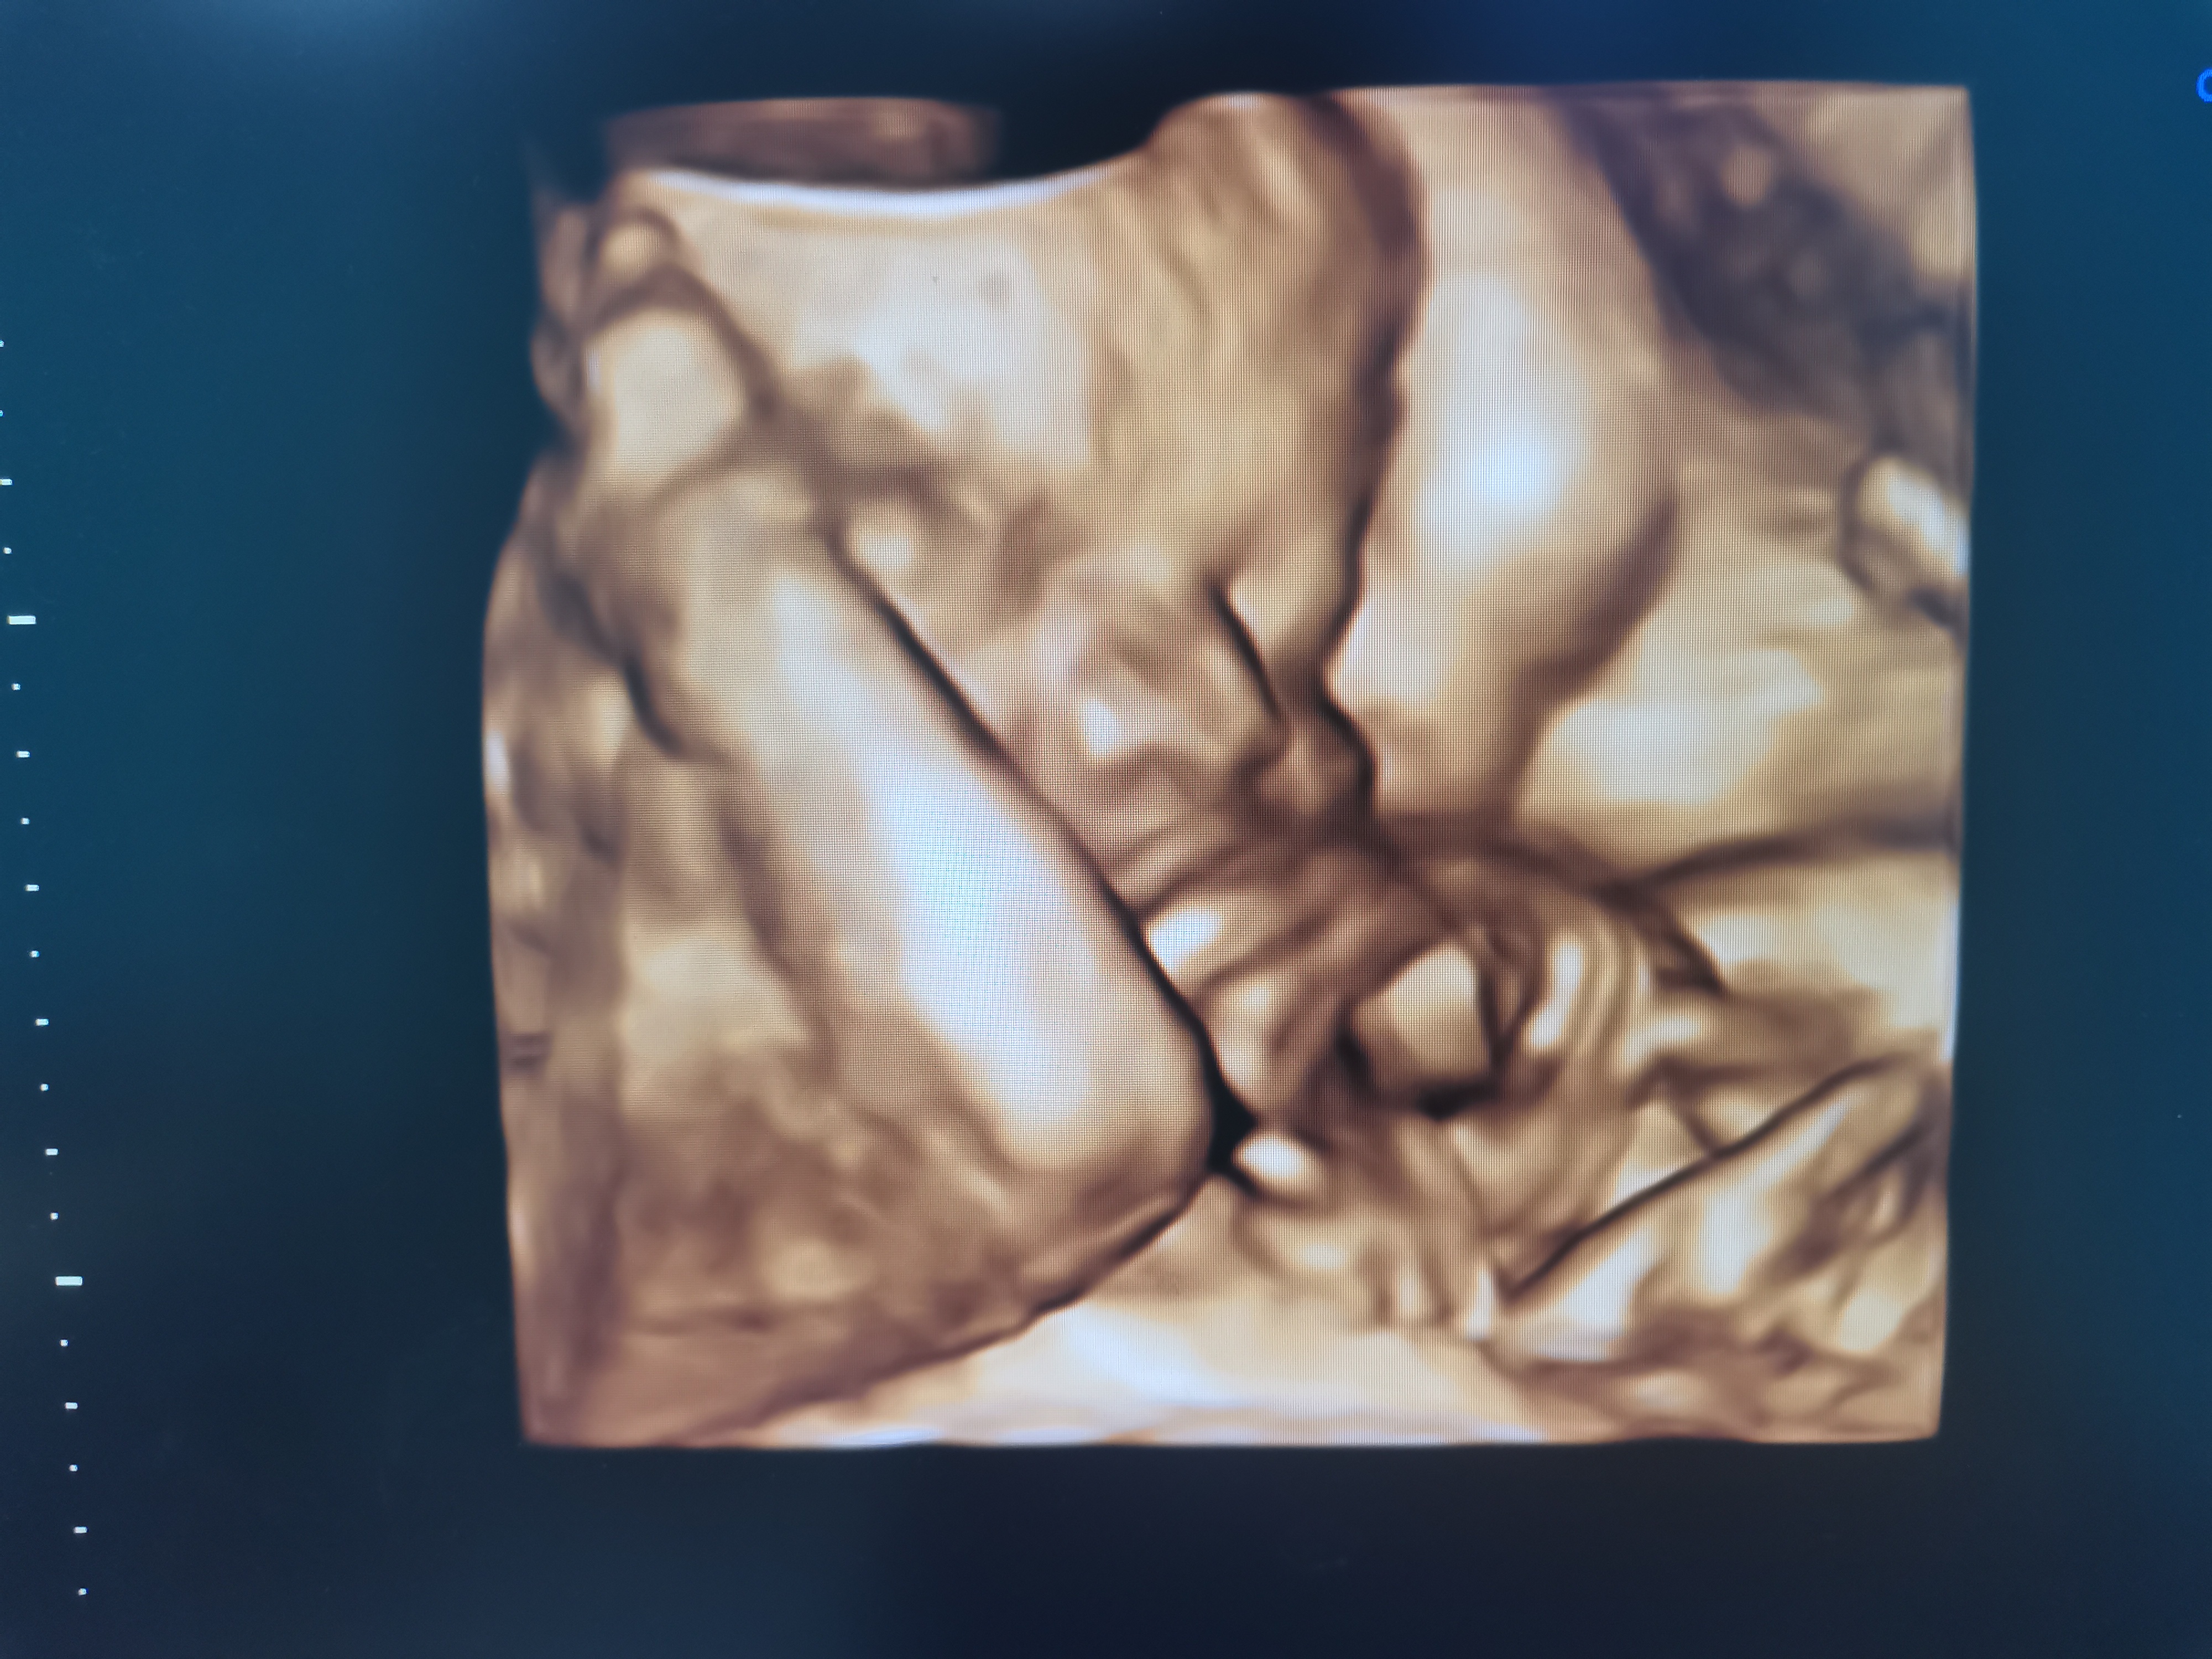

这些ultrasound都是我自己照的~呵呵

记录我小宝宝从小到大~

然后我一有空就照照看,看是不是可以看到他的脸~

不过他总是用手遮着,哈哈

在这里可以看到他的鼻子,侧面看有点像爸爸!

终于有一张是甘愿露脸的~baby就是真的不想让人看到他长什么样~哈哈